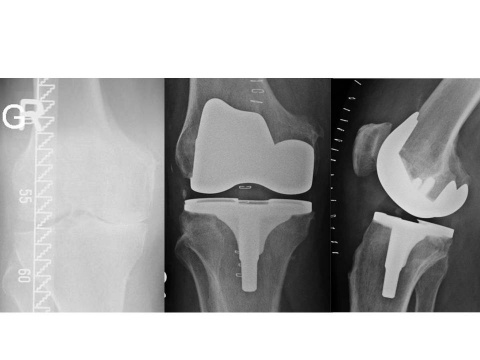

Hamburg, Deutschland) implantiert wurden. Für den Zuschnitt der Femurkondyle und des Tibiaplateaus wurde in der Gruppe mit dem PMI-System das System VisionaireTM (Smith&Nephew, Hamburg, Deutschland) genutzt. Im Zeitraum zwischen Januar 2008 und Dezember 2015 wurden im Hause 15 Patienten mit einer posttraumatischen Kniegelenksarthrose endoprothetisch versorgt. Hiervon waren zwei Patienten prä- und postoperativ auswertbar. Eine 63-jährige Patientin mit posttraumatischer Arthrose nach Tibiakopffraktur (Abb. 1) wurde mittels PMI-System versorgt (Abb. 2). Ein weiterer Patient (72 Jahre alt) wurde mit herkömmlicher Implantation versorgt (Abb. 3). Die Daten der Outcomes wurden mit hauseigenen Daten von 87 Patienten mit herkömmlicher Implantation und 84 Patienten mit PMI-gestützter Implantation verglichen. Das Durchschnittsalter der Patienten lag bei 71 respektive 66 Jahren. Das funktionelle Outcome wurde anhand des Oxford Knee Score und des Bewegungsumfanges beurteilt. Das radiologische Ergebnis wurde über die Veränderung der Knieachse sowie durch Bestimmung des medialen proximalen Tibia- und des distalen lateralen Femurwinkels (MPTA bzw. LDFA) in der Ganzbeinstandaufnahme sowie in der Messung des Slope in der seitlichen Aufnahme des Kniegelenks beurteilt. Es erfolgte die deskriptive Statistik mit Ermittlung von Maximum, Minimum, Mittelwert und Standardabweichung. Die Signifikanzprüfung erfolgte mittels Mann-Whitney-U-Test, wobei ein p-Wert von < 0,05 als signifikant angesehen wurde. Die statistische Auswertung aller Parameter erfolgte mit SPSS (Version 21.0).

Der Patient mit herkömmlich versorgter posttraumatischer Gonarthrose hatte postoperativ einen MPTA von 83° sowie einen mLDFA von 98°. Der Slope lag bei 12,4° und die Lastachse kreuzte das Tibiaplateau 7 mm medial des Fujisawapunktes. Den radiologischen Verlauf zeigt Abbildung 3.